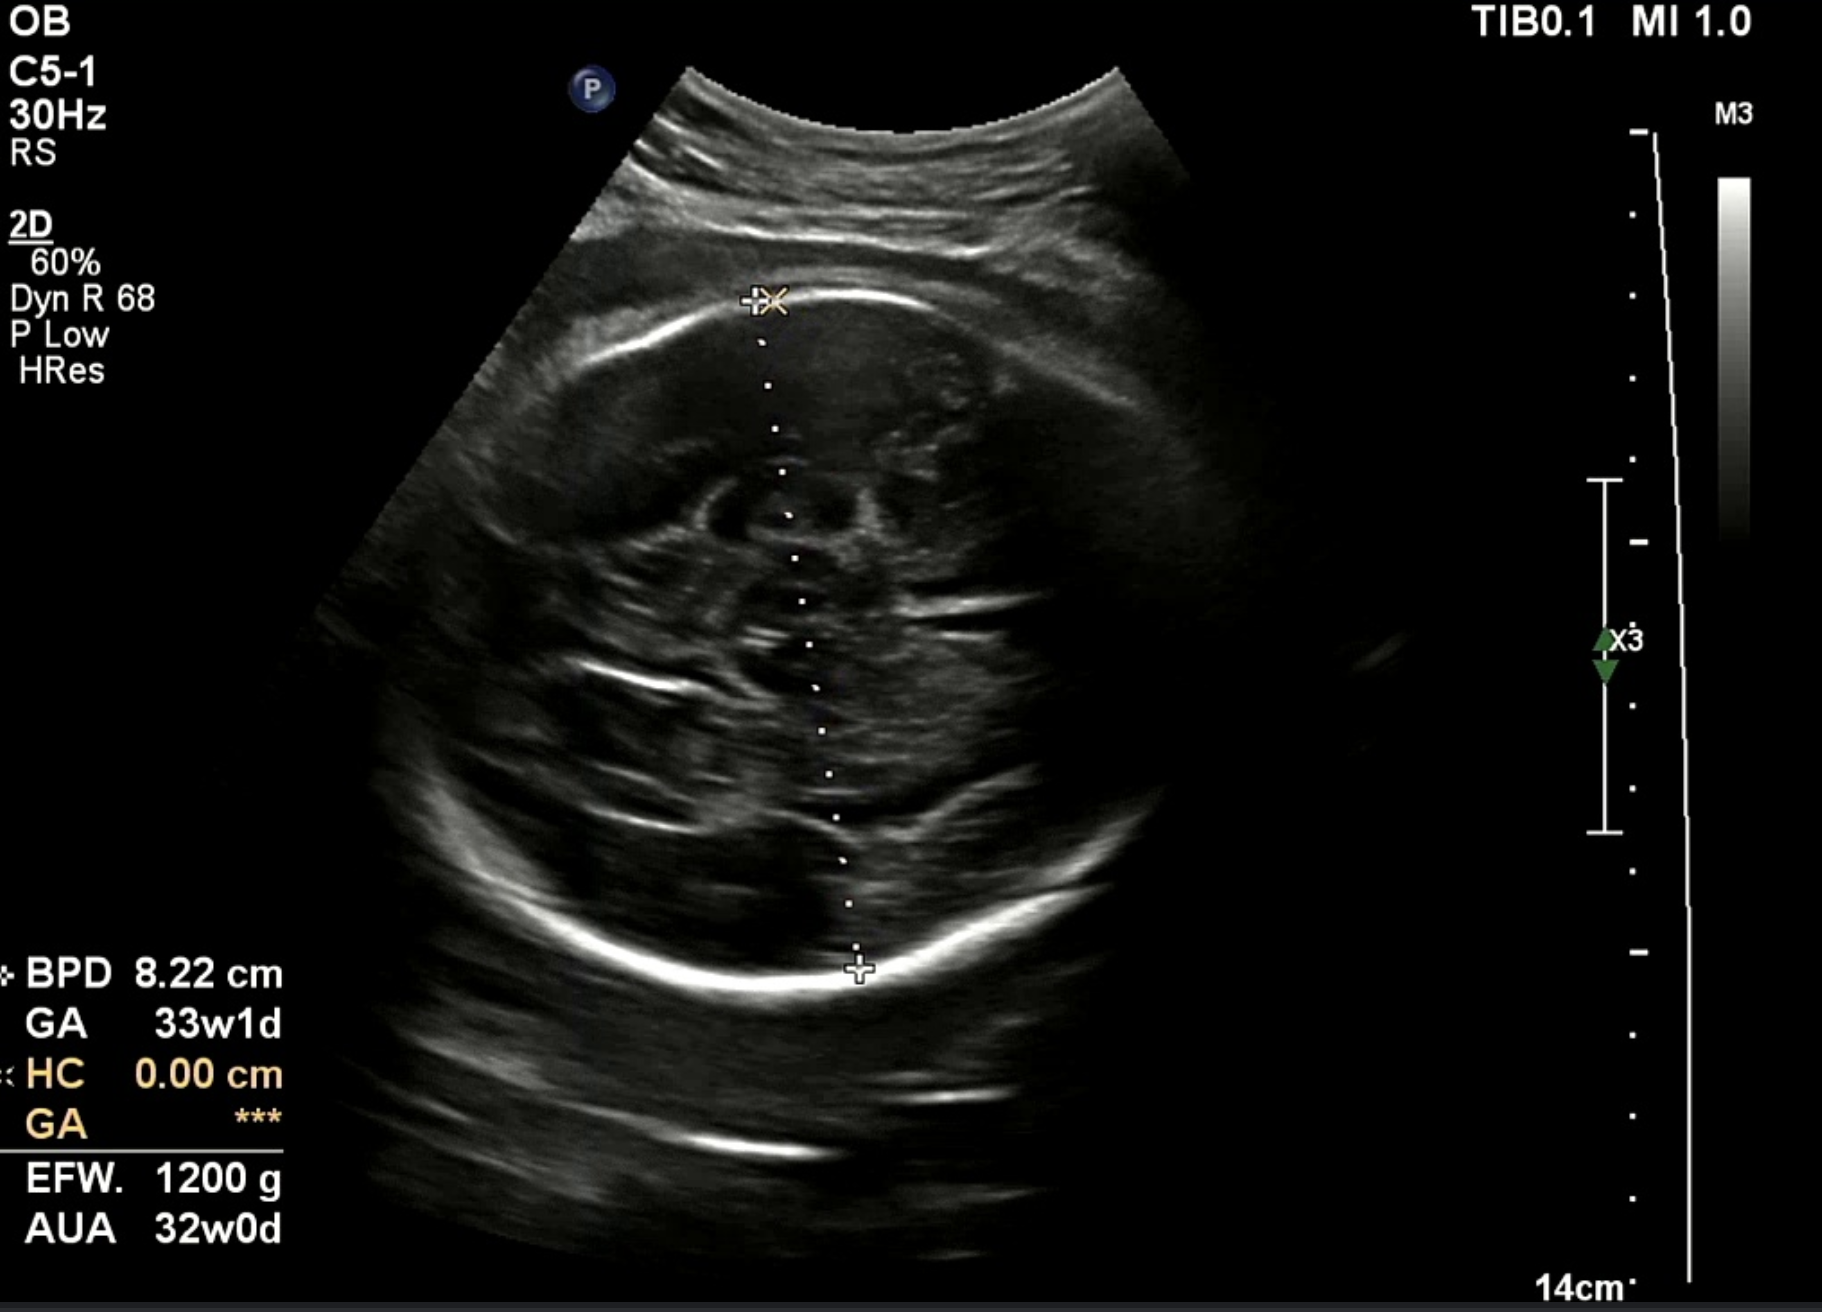

대부분의 녹화본에는 스케일바가 있다. 여기서 픽셀 당 실제거리 (cm/pixel) 을 구할 수 있다고 판단했다. 그래서 내가 원하는 두 점 사이의 거리 (단순 픽셀 거리) 곱하기 cm/pixel 을 곱하면 실제 거리를 구할 수 있다고 생각했다. cm/pixel 이 배율인 셈이다.

실제로는 8.22 cm 로 기록되었고 내가 측정한 기록값은 8.29 cm 로 오차는 크지 않았다. 가설을 검증했고 충분히 해볼 만하고 생각했다. 다만 아래와 같은 해결 과제가 남았다. 첫 번째는 계산 시 (14 cm / 스케일 바 픽셀 거리) 로 하드코딩해서 배율을 계산했기 때문에 스케일 바를 검출하는 이미지 전처리 과정이 필요했다. 두 번째는 초록색 영역 검출 시 곡선과 같은 형태 두 개를 찾고 그 사이 거리를 찾는 식이라 이미지별로 다소 편차가 있었다. 내 눈에는 원처럼 보이는데 컴퓨터가 인식할 때는 원으로 인식하지 않아서 반원 곡선 형태를 찾도록 코딩했다.